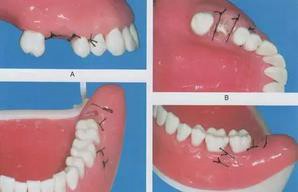

9.縫合

縫合不宜過(guò)于嚴(yán)密,通常第二磨牙遠(yuǎn)中處可以不縫,這樣既可達(dá)到縫合目的,又可使傷口內(nèi)的出血和反應(yīng)性產(chǎn)物得以引流,從而減輕術(shù)后腫脹和血腫的形成??p合時(shí),先縫合組織瓣的解剖標(biāo)志點(diǎn),如切口的切角和牙齦乳頭,這樣可以避免縫合時(shí)組織瓣移位。縫合完成后用消毒棉卷覆蓋拔牙創(chuàng)并囑患者咬緊加壓止血。